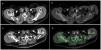

During the 6-month follow-up, the only MIRP in which a pathological parathyroid gland was not demonstrated histopathologically presented biochemical cure, which is an exceptional clinical circumstance6. Two presented persistent hypercalcemia, despite resection of an adenoma; one was recently and successfully reoperated on (Fig. 1) after finding a new parathyroid lesion (MIBI and PET-positive). The provisional cure rate was 97.5%.

Patient with PHPT who underwent resection of a parathyroid adenoma (yellow arrow) located posterior to the caudal pole of the left thyroid lobe (A) by means of MIRP after ultrasound-guided administration of 99mTc-MAA. The transaxial fusion SPECT/CT image shows the correct intralesional location of the radiotracer (B). Hypercalcemia persisted one year later, and a new parathyroid lesion was observed (C) in a more caudal right paraesophageal ectopic location (red arrow) with significant uptake of 99mTc-MIBI as shown in the SPECT/CT fusion image, (D) which was satisfactorily removed in a second surgery, this time radioguided with MIBI.